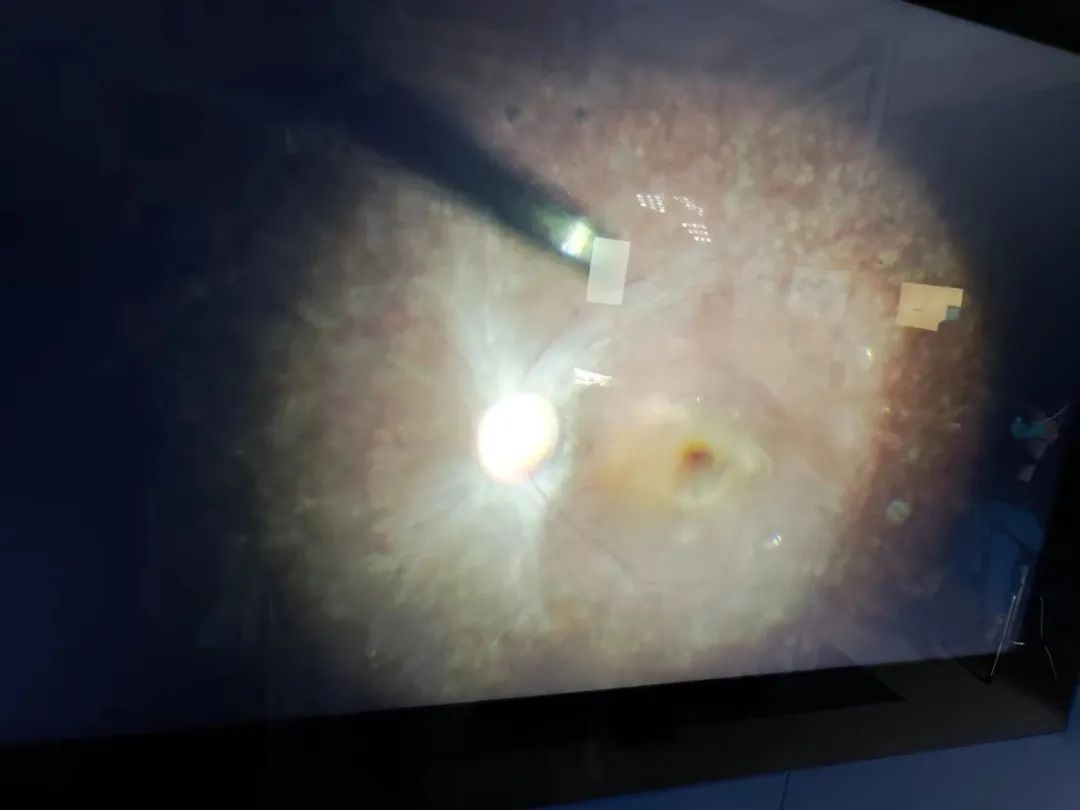

SHANGHAI and CLINTON, N.J., Apr. 10, 2023 - HuidaGene Therapeutics (HuidaGene), a global clinical-stage biotechnology company focused on developing genomic medicine, announced today that it has successfully completed the HG00401 clinical study "A study to evaluate gene therapy for RPE65 mutation in Leber's type 2 's congenital leukodystrophy (LCA2) with RPE65 mutation," the first patient was given a single ocular injection of the new gene therapy HG004.

The patient was evaluated in detail before and after admission, and the preoperative preparation was improved, and the patient was administered by Director Peiquan Zhao. Within 2 weeks after low-dose HG004 administration, this subject had a good safety profile and no serious adverse events, ocular adverse reactions (no intraocular inflammation was observed), significant drug-related adverse events, or clinically significant immune reactions were observed. The patient's study eye showed rapid and sustained improvement in best-corrected visual acuity in addition to relevant visual function indicators (e.g., dynamic visual field, full visual field stimulation threshold). At the same time, the patient indicated that the study eye could see things that could not be seen before surgery even in cloudy or dim environment, which gave him a great confidence to look forward to a more convenient life in the future.